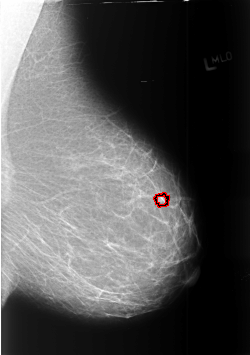

B_3372_1.LEFT_MLO

LEFT_MLO LINES 5672 PIXELS_PER_LINE 3992 BITS_PER_PIXEL 12 RESOLUTION 50 OVERLAY

FILE: B_3372_1.LEFT_MLO.OVERLAY

TOTAL_ABNORMALITIES 1

ABNORMALITY 1

LESION_TYPE MASS SHAPE IRREGULAR MARGINS SPICULATED

ASSESSMENT 4

SUBTLETY 2

PATHOLOGY MALIGNANT

TOTAL_OUTLINES 1

BOUNDARY